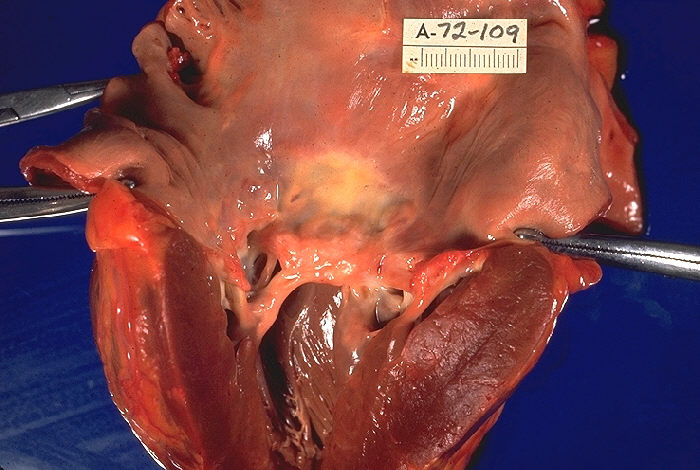

The mitral valve is the most affected cardiac valve.

Small vegetations accrue on the valve along the lines of closure that result in mitral regurgitation.

Chronic rheumatic heart disease develops when rheumatic fever-related valve scarring leads to stenosis with the classic fish-mouth appearance.

In chronic rheumatic heart disease, the chordae tendineae and cusps thicken as a result of the mitral valve being involved almost always.

Quite often the aortic valve is involved, which results in the commissures fusing together.